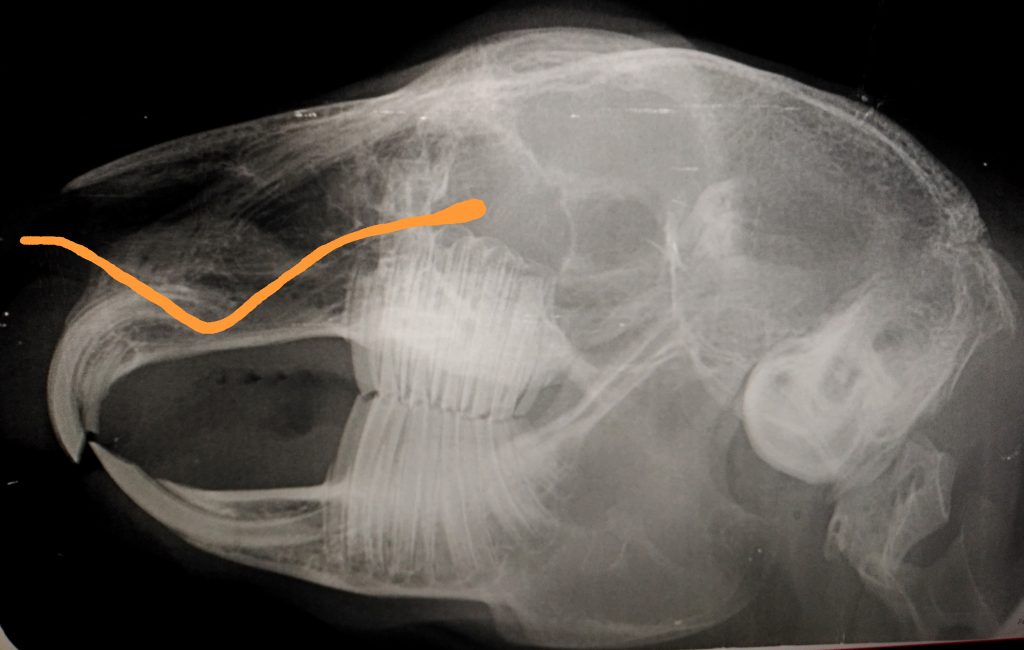

Die häufigste Ursache für eine Dakryozystitis ist eine Zahnproblematik: Entzündungen der Zahnwurzel, damit ist die im Zahnfleisch liegende Wachstumszone des Zahnes gemeint, greifen oft auf den dort sehr nah verlaufenden Tränennasenkanal über oder eine Verlängerung der Zahnwurzel engt den Tränennasenkanal (TNK siehe Röntgenbild) ein bzw. es wird ein mechanischer Druck ausgeübt, was zu einem Sekretstau führt, der einen guten Nährboden für Bakterien bildet. Der TNK beim Kaninchen verläuft vom Augenwinkel des Unterlids, mündet seitlich innerhalb der Nase und sitzt teilweise sehr dicht an den Zahnwurzeln, vor allem an zwei der Prämolaren (Prämolare und Molare bilden zusammen die Backenzähne der Kaninchen), der beiden vorderen Backenzähne im Oberkiefer und der Schneidezähne.

Das Bild zeigt eine Röntgenaufnahme eines Kaninchenschädels. Dort ist der Verlauf der Tränennasenkanals eingezeichnet.